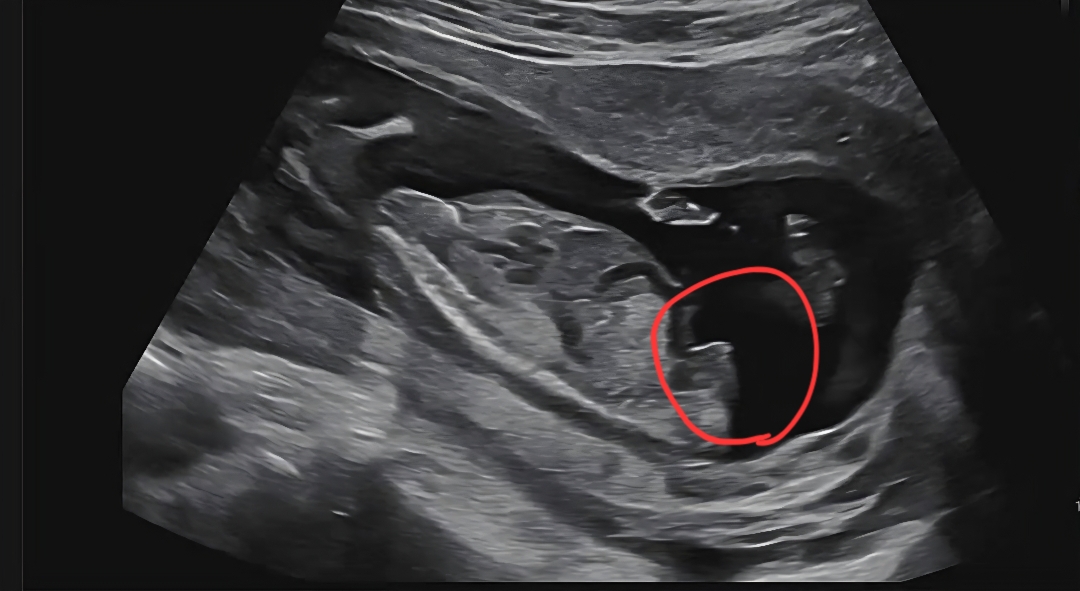

아들일까요?

고추?

아들같아영

아들같은데요??